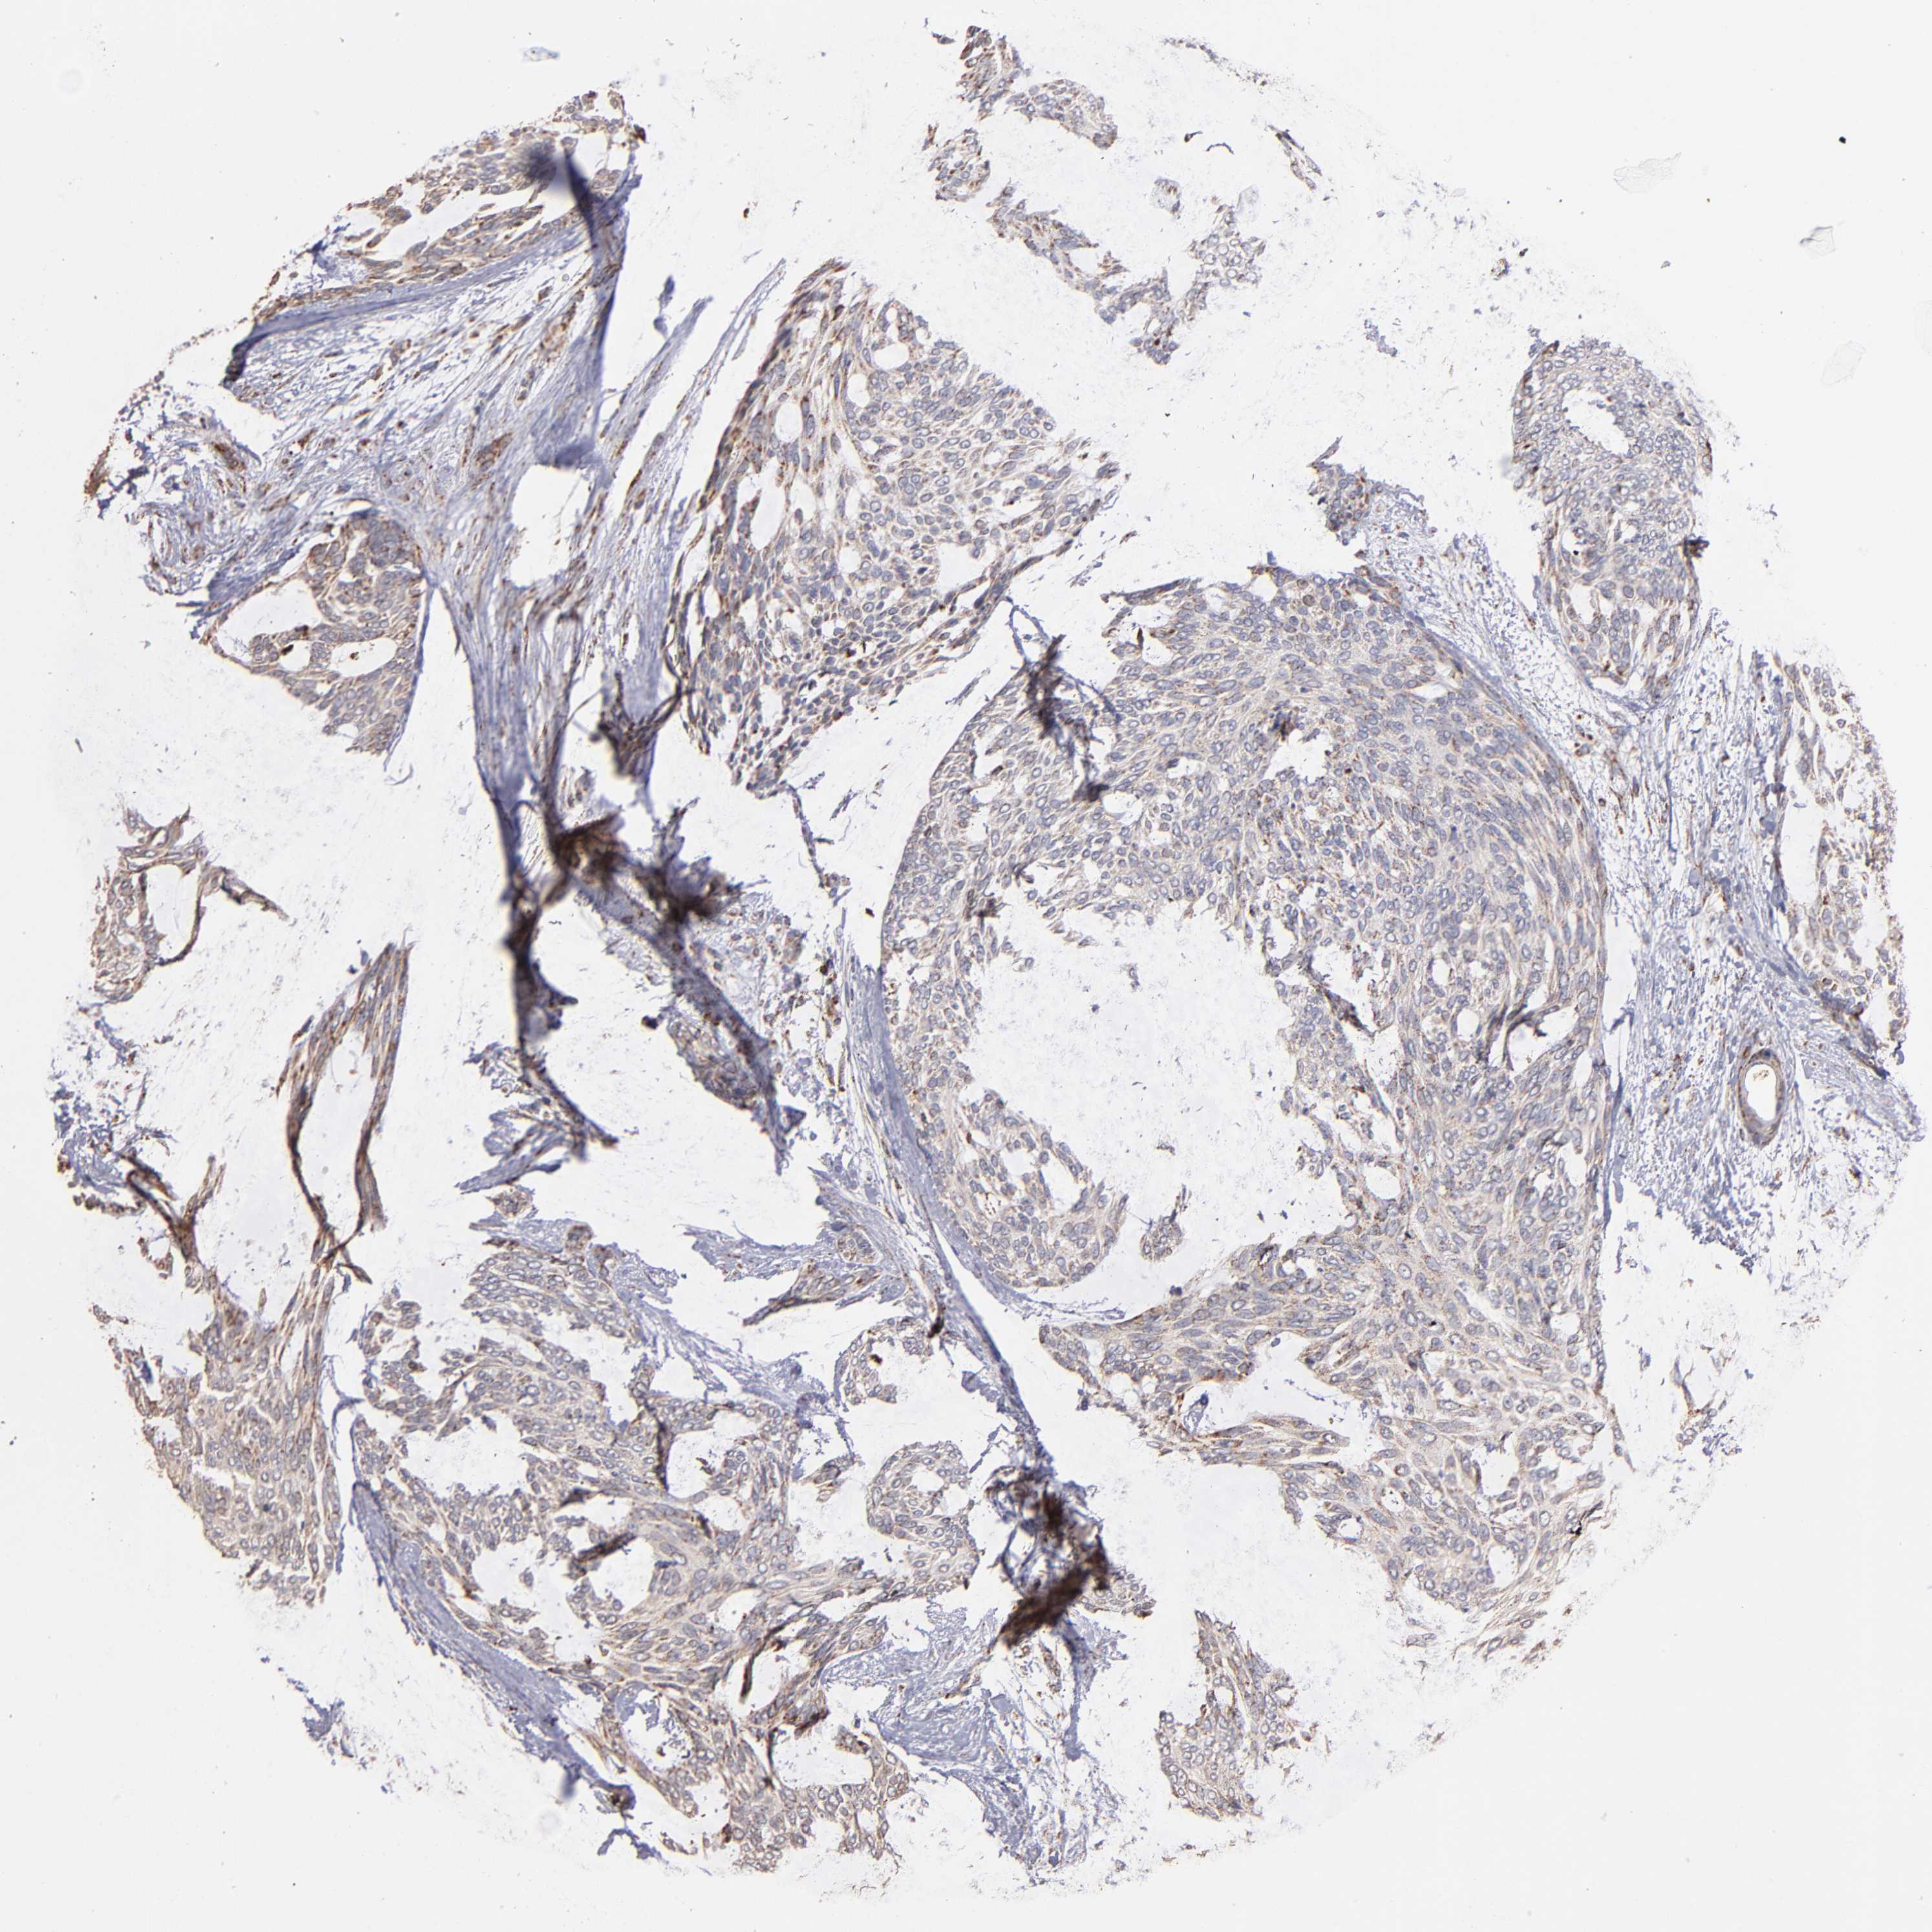

SKIN CANCER - Protein expressioni

A mouse-over function shows sample information and annotation data. Click on an image to view it in a full screen mode. Samples can be filtered based on level of antibody staining by selecting one or several of the following categories: high, medium, low and not detected. The assay and annotation is described here.

Antibody stainingi

Antibody staining in the annotated cell types in the current human tissue is reported as not detected, low, medium, or high, based on conventional immunohistochemistry profiling in selected tissues. This score is based on the combination of the staining intensity and fraction of stained cells.

Each image is clickable and will lead to virtual microscopy that enables deeper exploration of all samples and also displays staining intensity scores, fraction scores and subcellular localization as well as patient and tissue information for each sample.

Antibody HPA003010

Staining

High

Medium

Low

Not detected

Intensity

Strong

Moderate

Weak

Negative

Quantity

>75%

75%-25%

<25%

None

Location

Nuclear

Cytoplasmic/membranous

Cytoplasmic/membranous,nuclear

Squamous cell carcinoma, NOS

Basal cell carcinoma